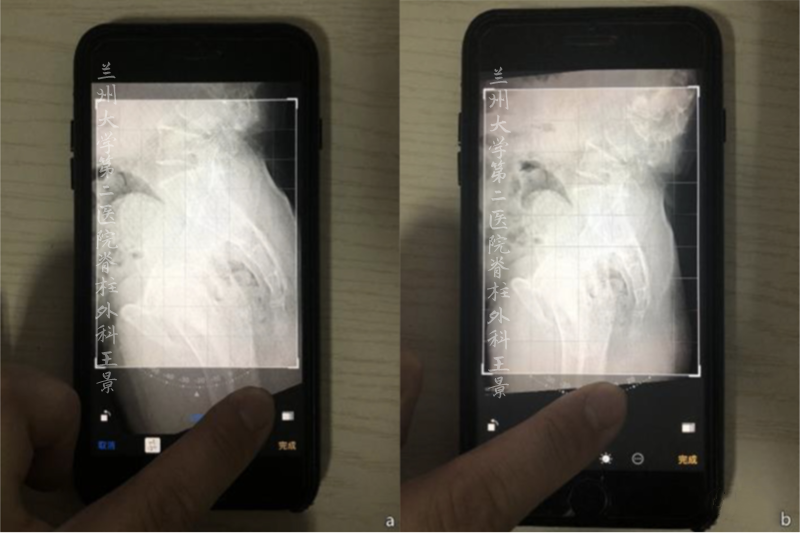

掏出iPhone,尽量正对拍摄

实际上稍微歪一点也没关系

打开照片,进入编辑模式

手指按着屏幕旋转照片

iOS自带的功能

图片旋转时会显示网格线及旋转角度

顺时针/逆时针旋转分别显示±°

精度为1°

如图所示旋转照片

S1上终板与水平线重叠/平行

旋转角度就是骶骨倾斜角

即SS=32°

再重新旋转图片

让股骨头中垂线与网格垂线重叠

旋转角度就是PT(-8°)